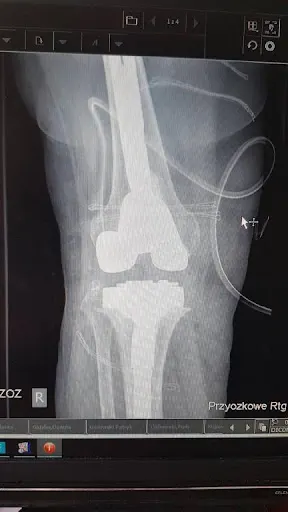

### Lek. med. Piotr Zawadzki – ortopeda w Gdyni W sercu Gdyni, przy alei Piłsudskiego 30, prowadzi praktykę lek. med. Piotr Zawadzki, specjalista w dziedzinie ortopedii. Gabinet zlokalizowany w dogodnym punkcie miasta (kod pocztowy 81-378) przyciąga pacjentów z regionu, którzy wystawiają mu doskonałe oceny. Średnia 5.0 na 5 w Google, oparta na 12 opiniach, świadczy o wysokim poziomie zadowolenia klientów. Pacjenci doceniają doktora za konkretność i profesjonalizm. Wielu z nich podkreśla, że dr Zawadzki szybko stawia trafną diagnozę – czasem w kilkanaście minut – tam, gdzie inni specjaliści przez lata nie potrafili wyjaśnić problemu. Słucha uważnie, doradza i prowadzi przez cały proces leczenia, w tym wyznacza terminy operacji oraz zapewnia opiekę po zabiegu. Opinie wskazują, że nie odsyła z niczym, lecz szuka rozwiązań, co buduje zaufanie. Współpracujący z doktorem zespół lekarzy również zbiera pozytywne wzmianki. Pacjenci opisują go jako lekarza rzeczowego, który wyjaśnia chorobę w zrozumiały sposób, dając poczucie bezpieczeństwa. "Wiem, że jestem w dobrych rękach" – to częsty komentarz, potwierdzający skuteczność i empatię w codziennej praktyce. *(Słowa: 198)*